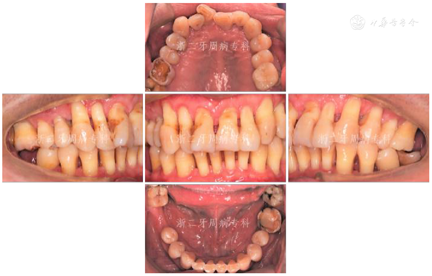

口腔卫生欠佳,软垢指数:2;牙石指数:3;全口牙龈充血红肿;平均牙周探诊深度(PD)7.0 mm,PD≥7 mm的位点占所有检查位点的63.3%(114/180),其中17颊侧远中、17舌侧远中、34舌侧远中、36颊侧近中、46舌侧近中PD深达12 mm;平均附着丧失(CAL)9.3 mm、CAL≥5 mm的位点数为98.3%(177/180);BOP(+)%:100%;37、46松动度Ⅲ度,11~17、21、22、24~27、32、34、41~43、45、47松动Ⅱ~Ⅲ度,余牙松动度Ⅰ度;36、46Ⅲ度根分叉病变。16、26、36、46牙釉质发育不Ⅲ全,11扭转,37缺失舌向倾斜,12、14~16、24、25、41、42咬合时出现异常动度,31、41可见1.5 mm左右牙间隙(图1,图2)。牙髓活力测定:17、34牙髓活力正常,36、37、46"40"无反应。

2008年9月:基础治疗完成后6个月牙周复诊,进行再评估,患者口腔卫生状况良好,牙龈炎症明显改善,PD≥7 mm的位点数从108个减少到4个,4~6 mm的位点数从61个减少到39个,平均探诊深度从7.0 mm降至3.0 mm,尤其是17远中2个位点,PD从12 mm分别降至3 mm(颊侧)与4 mm(舌侧);BOP(+)%从100%降到28.6%(图8)。各牙松动度较治疗前也明显改善,下前牙31、41仍有0.5 mm间隙。

2009年4月:牙周基础治疗后1年复诊。患者口腔卫生可,牙龈色粉质韧,仅下前牙舌侧可见少量软垢,局部龈缘充血(图9),并惊喜地发现:下前牙31、41间隙已完全关闭。牙齿松动度、PD、BOP(+)%与半年前无明显变化(图10)。全口曲面体层X片示:牙槽嵴顶硬骨板较2007年12月清晰,14、17、24、34、36局部有牙槽骨修复、36根尖周骨密度增加,其余位点牙槽骨均未见进一步吸收;46缺牙区牙槽骨密度和高度增加(图11),提示牙周基础治疗后牙周状况得到了明显改善。因37、46缺失牙未及时修复,16略伸长,38近中倾斜,再次建议患者正畸治疗,直立38、压入16,排齐整平牙列,修复缺失牙37、46。患者拒绝正畸和修复治疗。予以16调磨、牙周维护治疗、35~44超级粘结剂牙周固定。